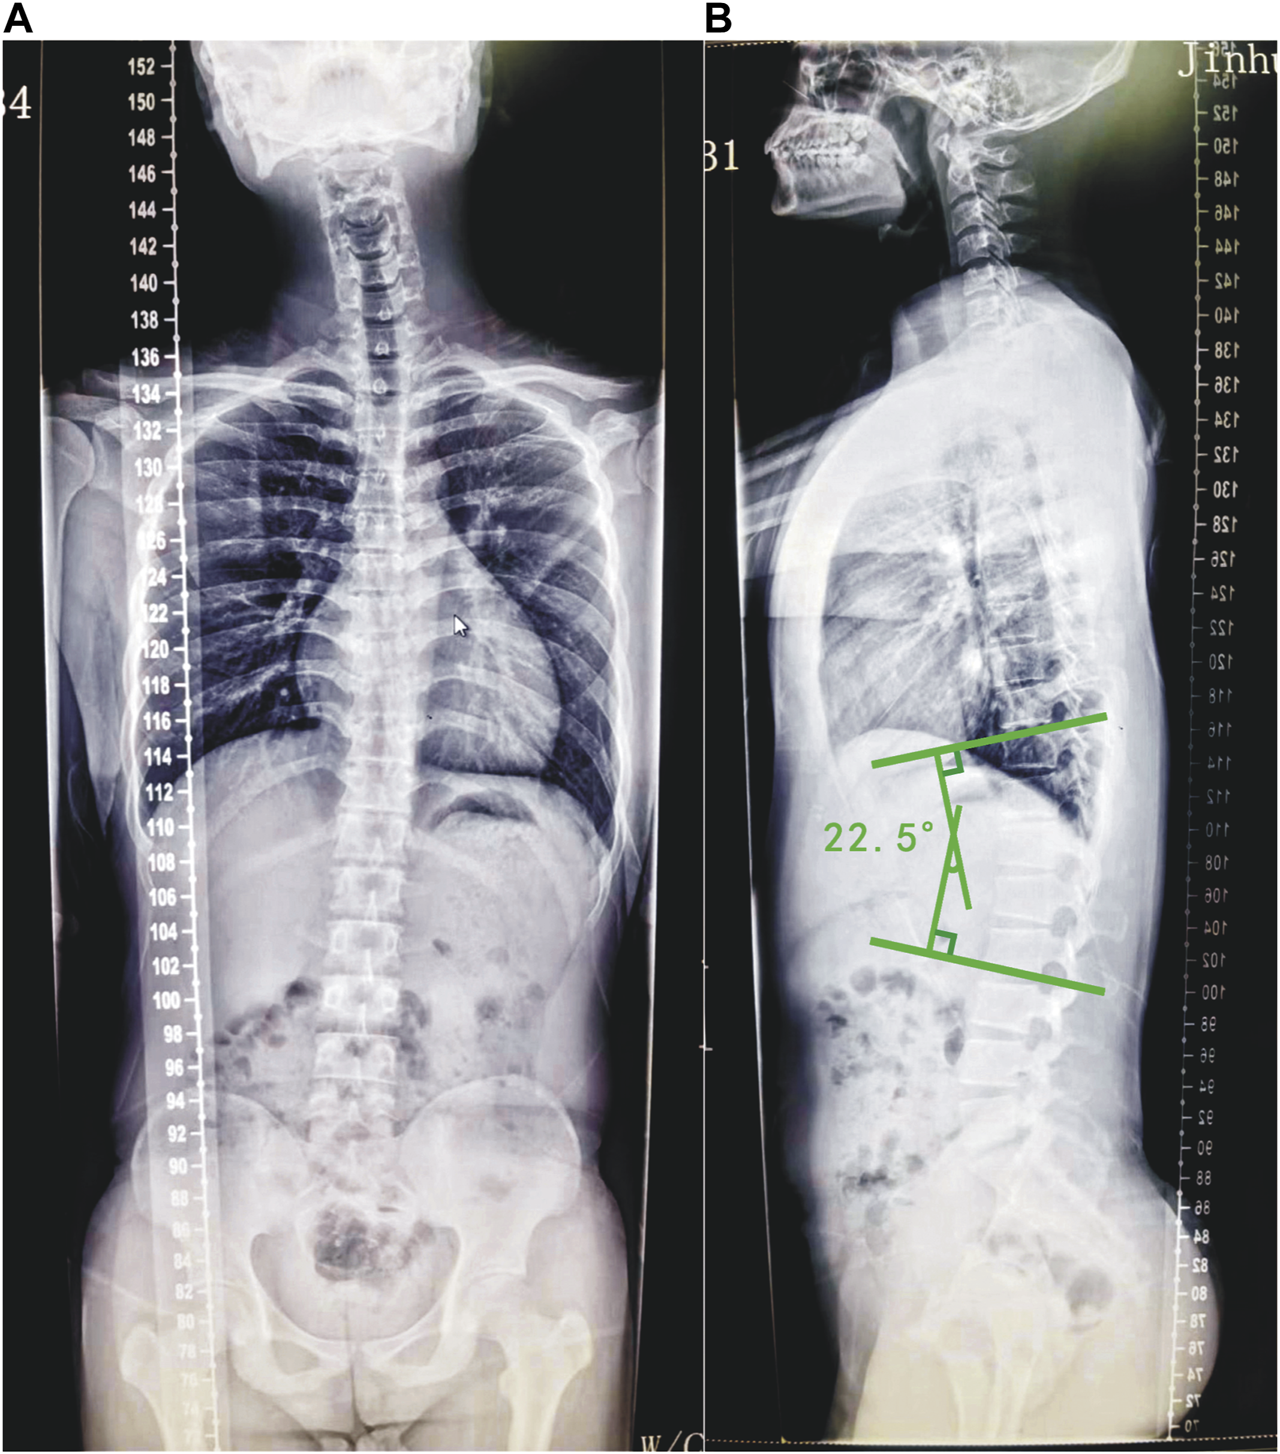

A total of 20 Scheuermann’s disease patients with TLK and 20 cases of asymptomatic participants were recruited in this study. In the patient group, the mean age was 24.1 ± 3.5, whereas the mean age of the control group was 24.5 ± 3.5 (Table 1). Participants of both groups received spinal full-length anteroposterior and lateral radiographs (Philips TH-VS Dr) to determine compliance with the inclusion criteria (Macagno and O’Brien, 2006; Enad et al., 2008) prior to their participation in the study (Figure 1). The angle between the parallel line of the upper-end plate of T10 and the parallel line of the lower-end plate of L2 is Cobbs’ angle (Caesarendra et al., 2022). The Cobbs’ angle of the thoracolumbar segment on each patient’s lateral radiographs was measured using Surgimap software (Nemaris, Inc.). The mean Cobbs’ angle of the patients’ thoracolumbar segments was 15.1° ± 7.0°. The gait analysis model used Visual3D software (Visual3D, C-Motion, Inc., United States) and contained 7 bony segments, 6 joints, and 18 degrees of freedom.

FIGURE 1

www.frontiersin.org

FIGURE 1. Radiograph of a typical selected example of Scheuermann’s disease patients with TLK. The anterior–posterior (A) view of the full spine of the patient and the lateral (B) view of the full spine of the patient. Draw a parallel line along the upper endplate of the T10 vertebra and a parallel line along the lower endplate of the L2 vertebra. Then, make two lines that are vertical to the aforementioned two lines. The angle between the two vertical lines is Cobbs’ angle. The Cobbs’ angle of the patient’s thoracolumbar segment is 22.5°.